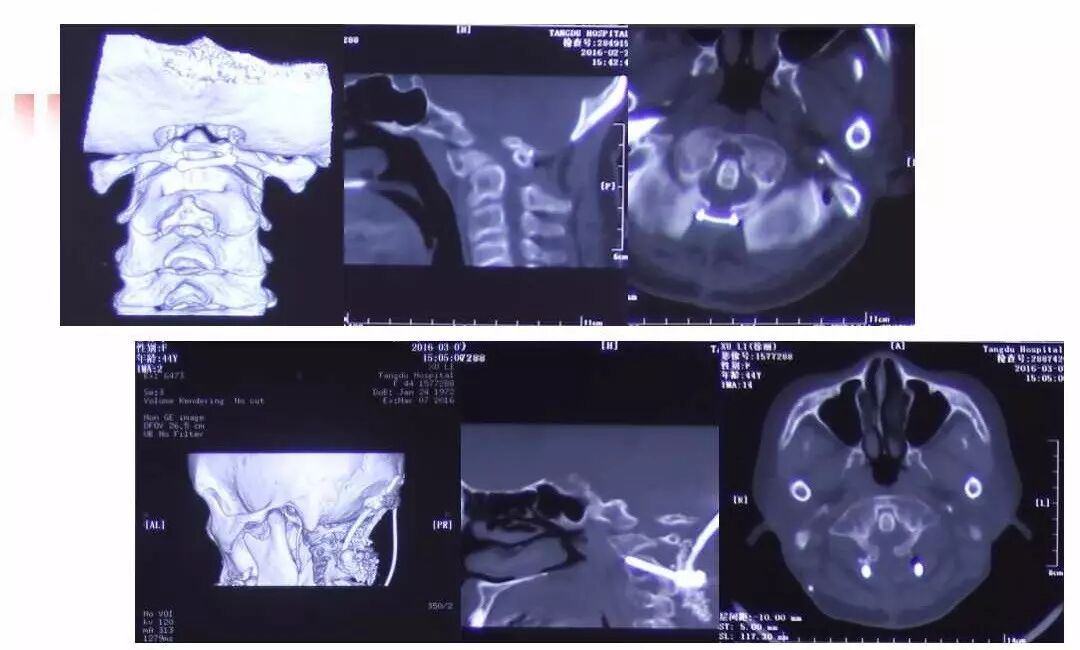

在脊柱神经外科、显微神经外科和颅底肿瘤外科前沿研究和临床诊治领域有着扎实的基础,为全国首批获得脊柱神经外科医师培训认证的神经外科医生。擅长颈椎病、椎管肿瘤及各种脊柱疑难疾病的诊治、脑肿瘤微创手术,尤其擅长颈椎退行性疾病的手术,率先在国内开展了颅底凹陷后路复位、颈前路减压融合等高难度手术,多年来收治了来自全国各地的大量患者,疗效达到国内领先水平。